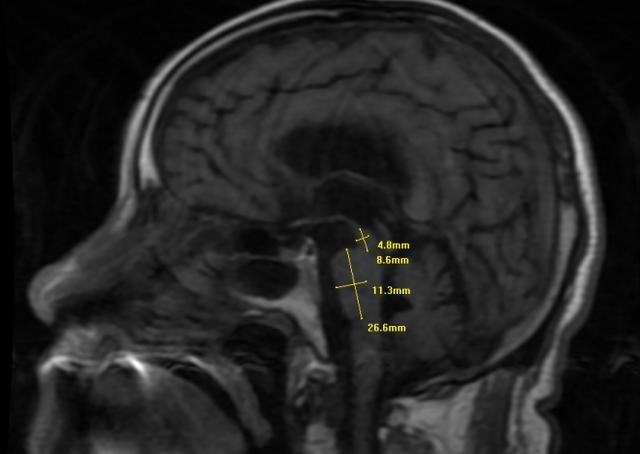

为了证实推断,医生调取了王大爷的脑部核磁共振图像。在脑干中脑部位的矢状位图像上,一个典型的特征出现了,熊猫体育官方中脑组织明显萎缩,侧面轮廓看起来就像一只蜂鸟的剪影。

它并非真的有一只鸟,而是中脑萎缩后,在影像上形成的特殊形态。正是这只“蜂鸟”,揭示了困扰老人三年的病根。